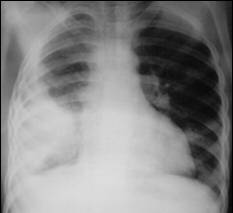

A loculated effusion

has an unusual

shape (lentiform) or

position in the

thoracic cavity

This is a loculated

empyema

Loculated Effusion